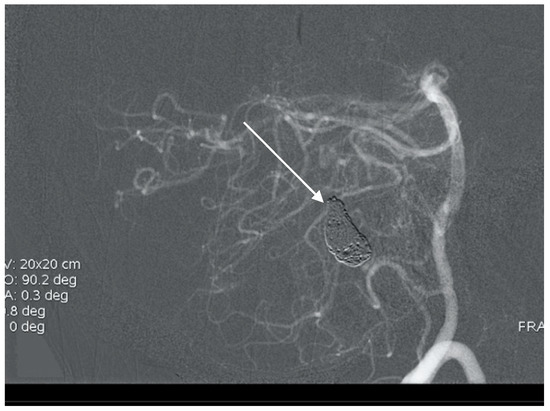

Figure 5. Oblique projection of an angiogram with three PICA aneurysms.

A 60-year-old woman was admitted for abrupt loss of consciousness. CT in a peripheral setting showed cerebellar hemorrhage with a pan-intraventricular hematoma in the fourth ventricle and a massive SAH in the cerebellar and spinal canal regions (Figure 4). AG revealed three aneurysms on the distal PICA (Figure 5), successfully excluded from circulation by microsurgery clipping while maintaining patency of the PICA. During the surgery, sudden intraoperative rupture occurred from the most peripheral aneurysm, located just under the arachnoid membrane on the surface of the cerebellum. After easy clipping of the neck, the feeding vessel was followed in the hematoma to its telovelotonsillar part, where another two aneurysms were visible. With the technique of temporary clipping, the optimal final position on both clips was achieved in the wide necked aneurysms. The patency was confirmed with intraoperative ultrasound. A difficult postoperative course and hydrocephalus required temporary ventricular drainage, which was converted to a ventriculo peritoneal (VP) shunt with a good long-term result.